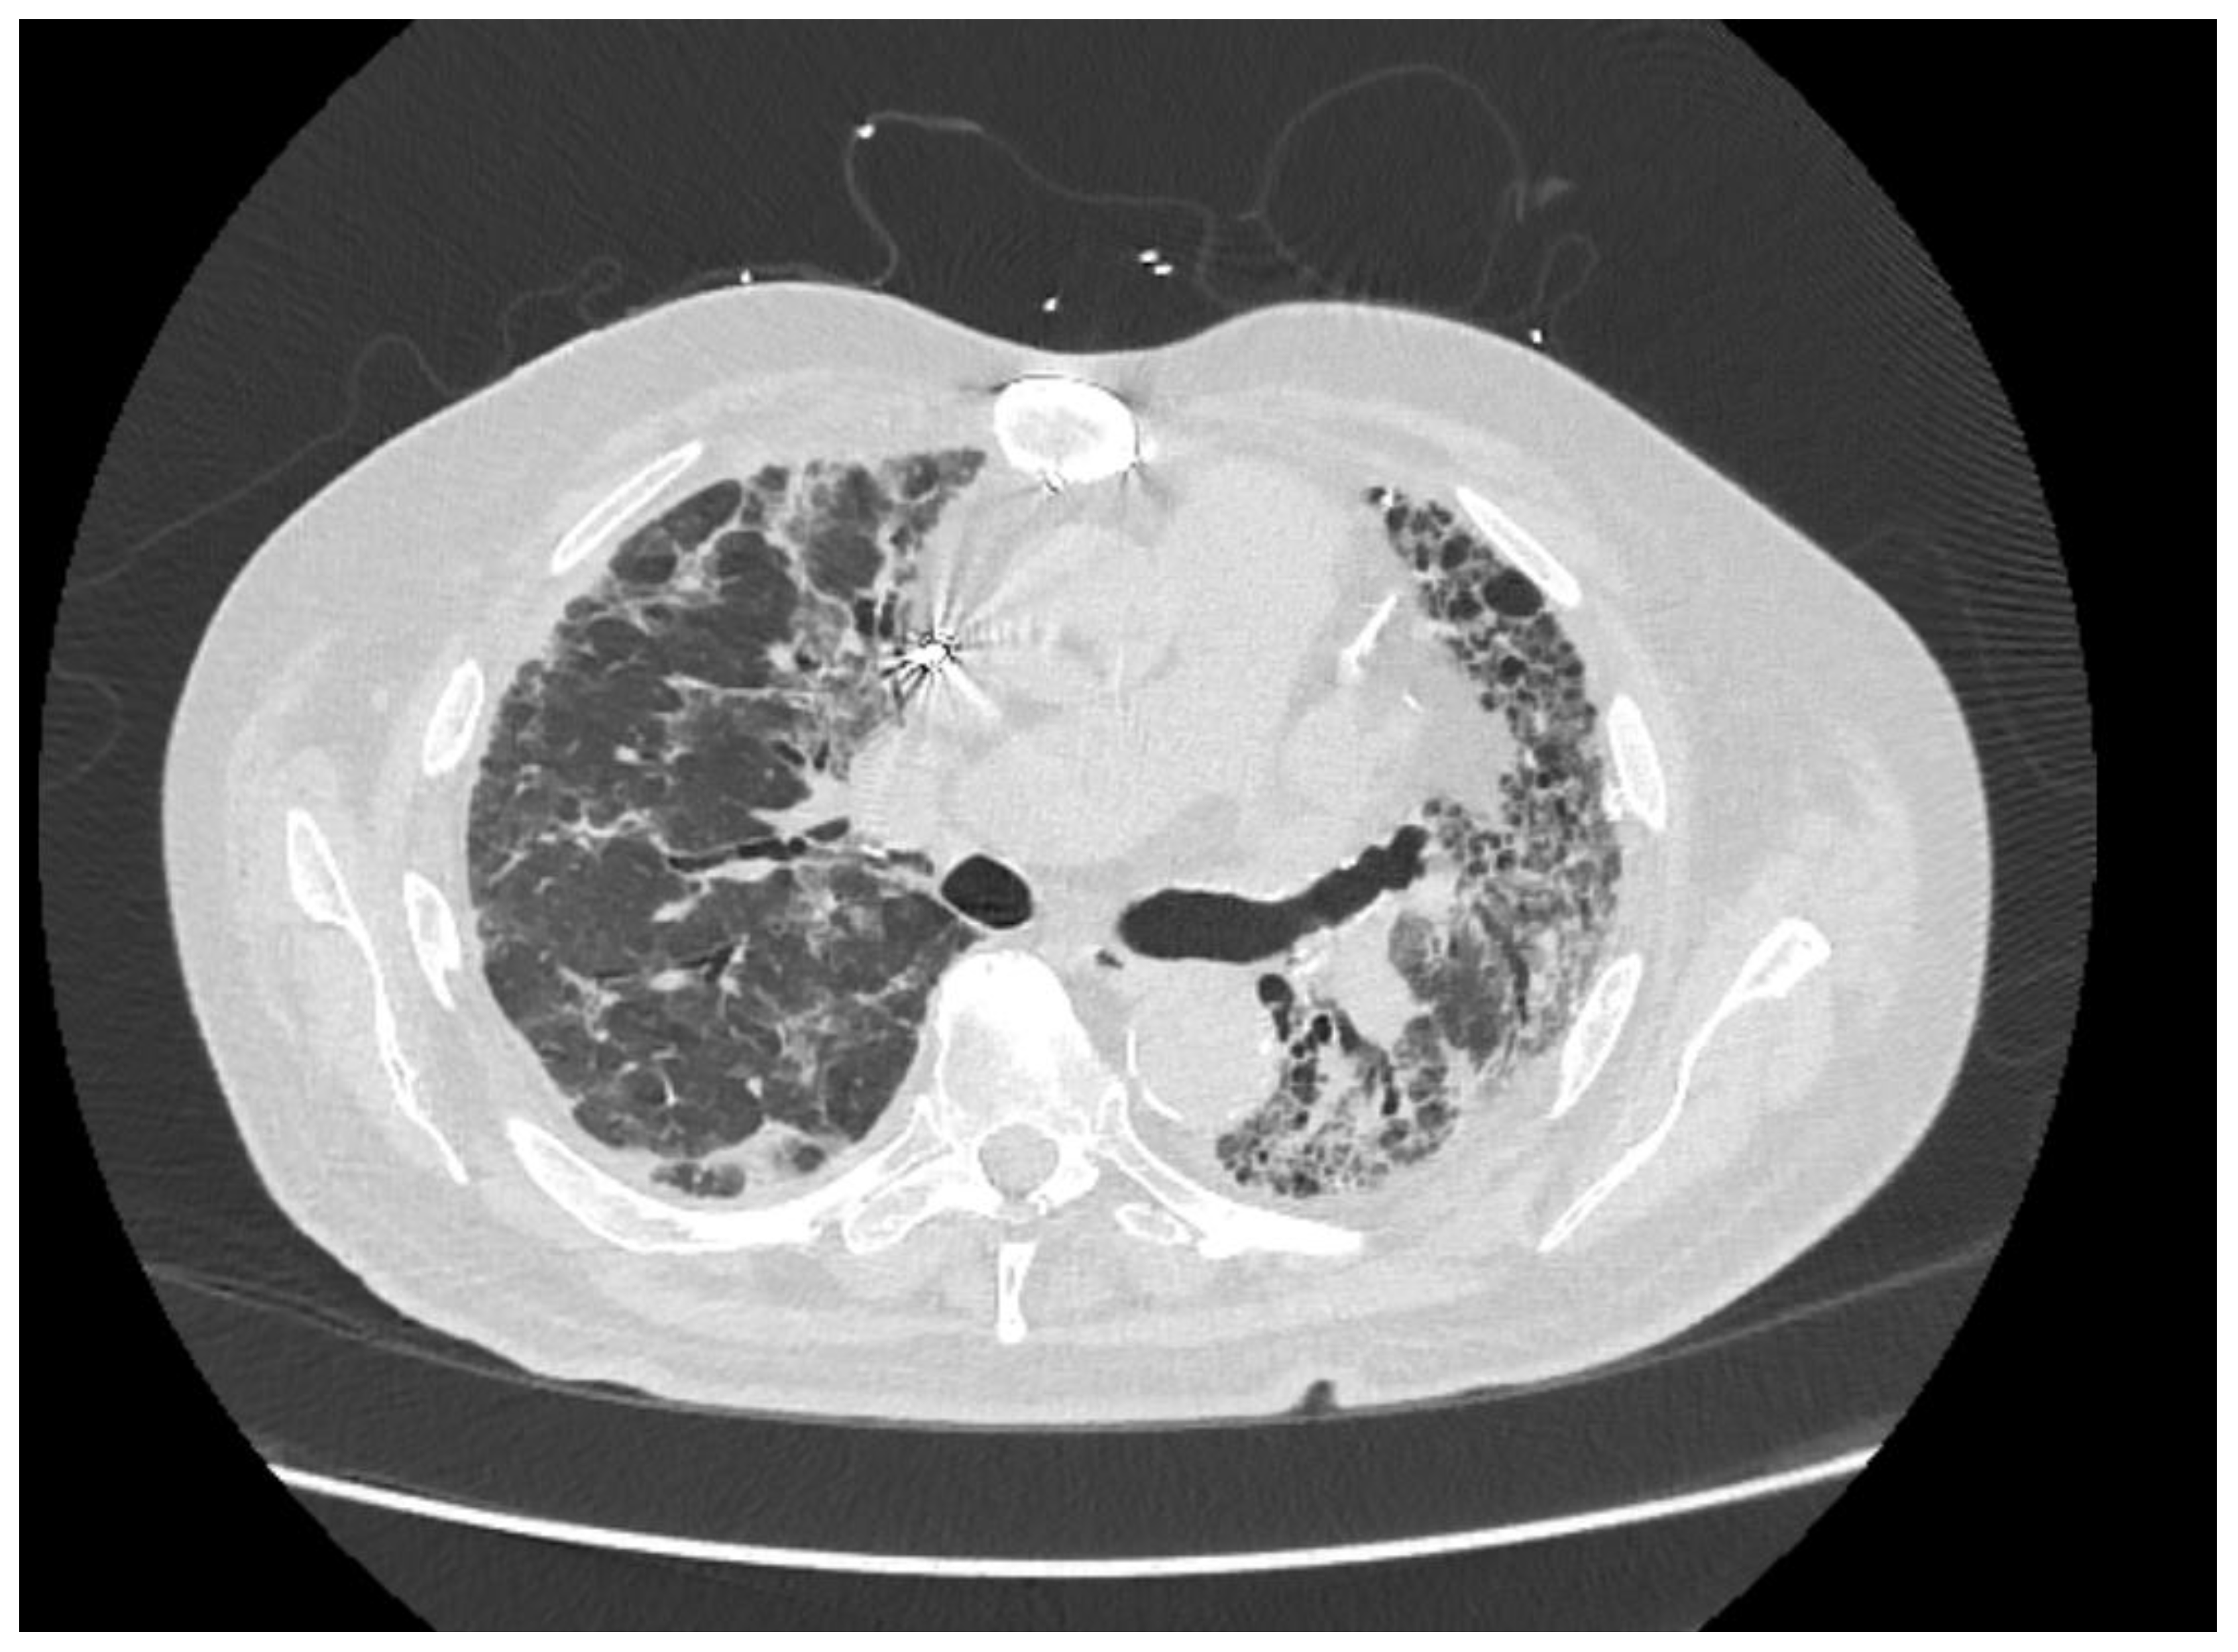

2. Case Presentation